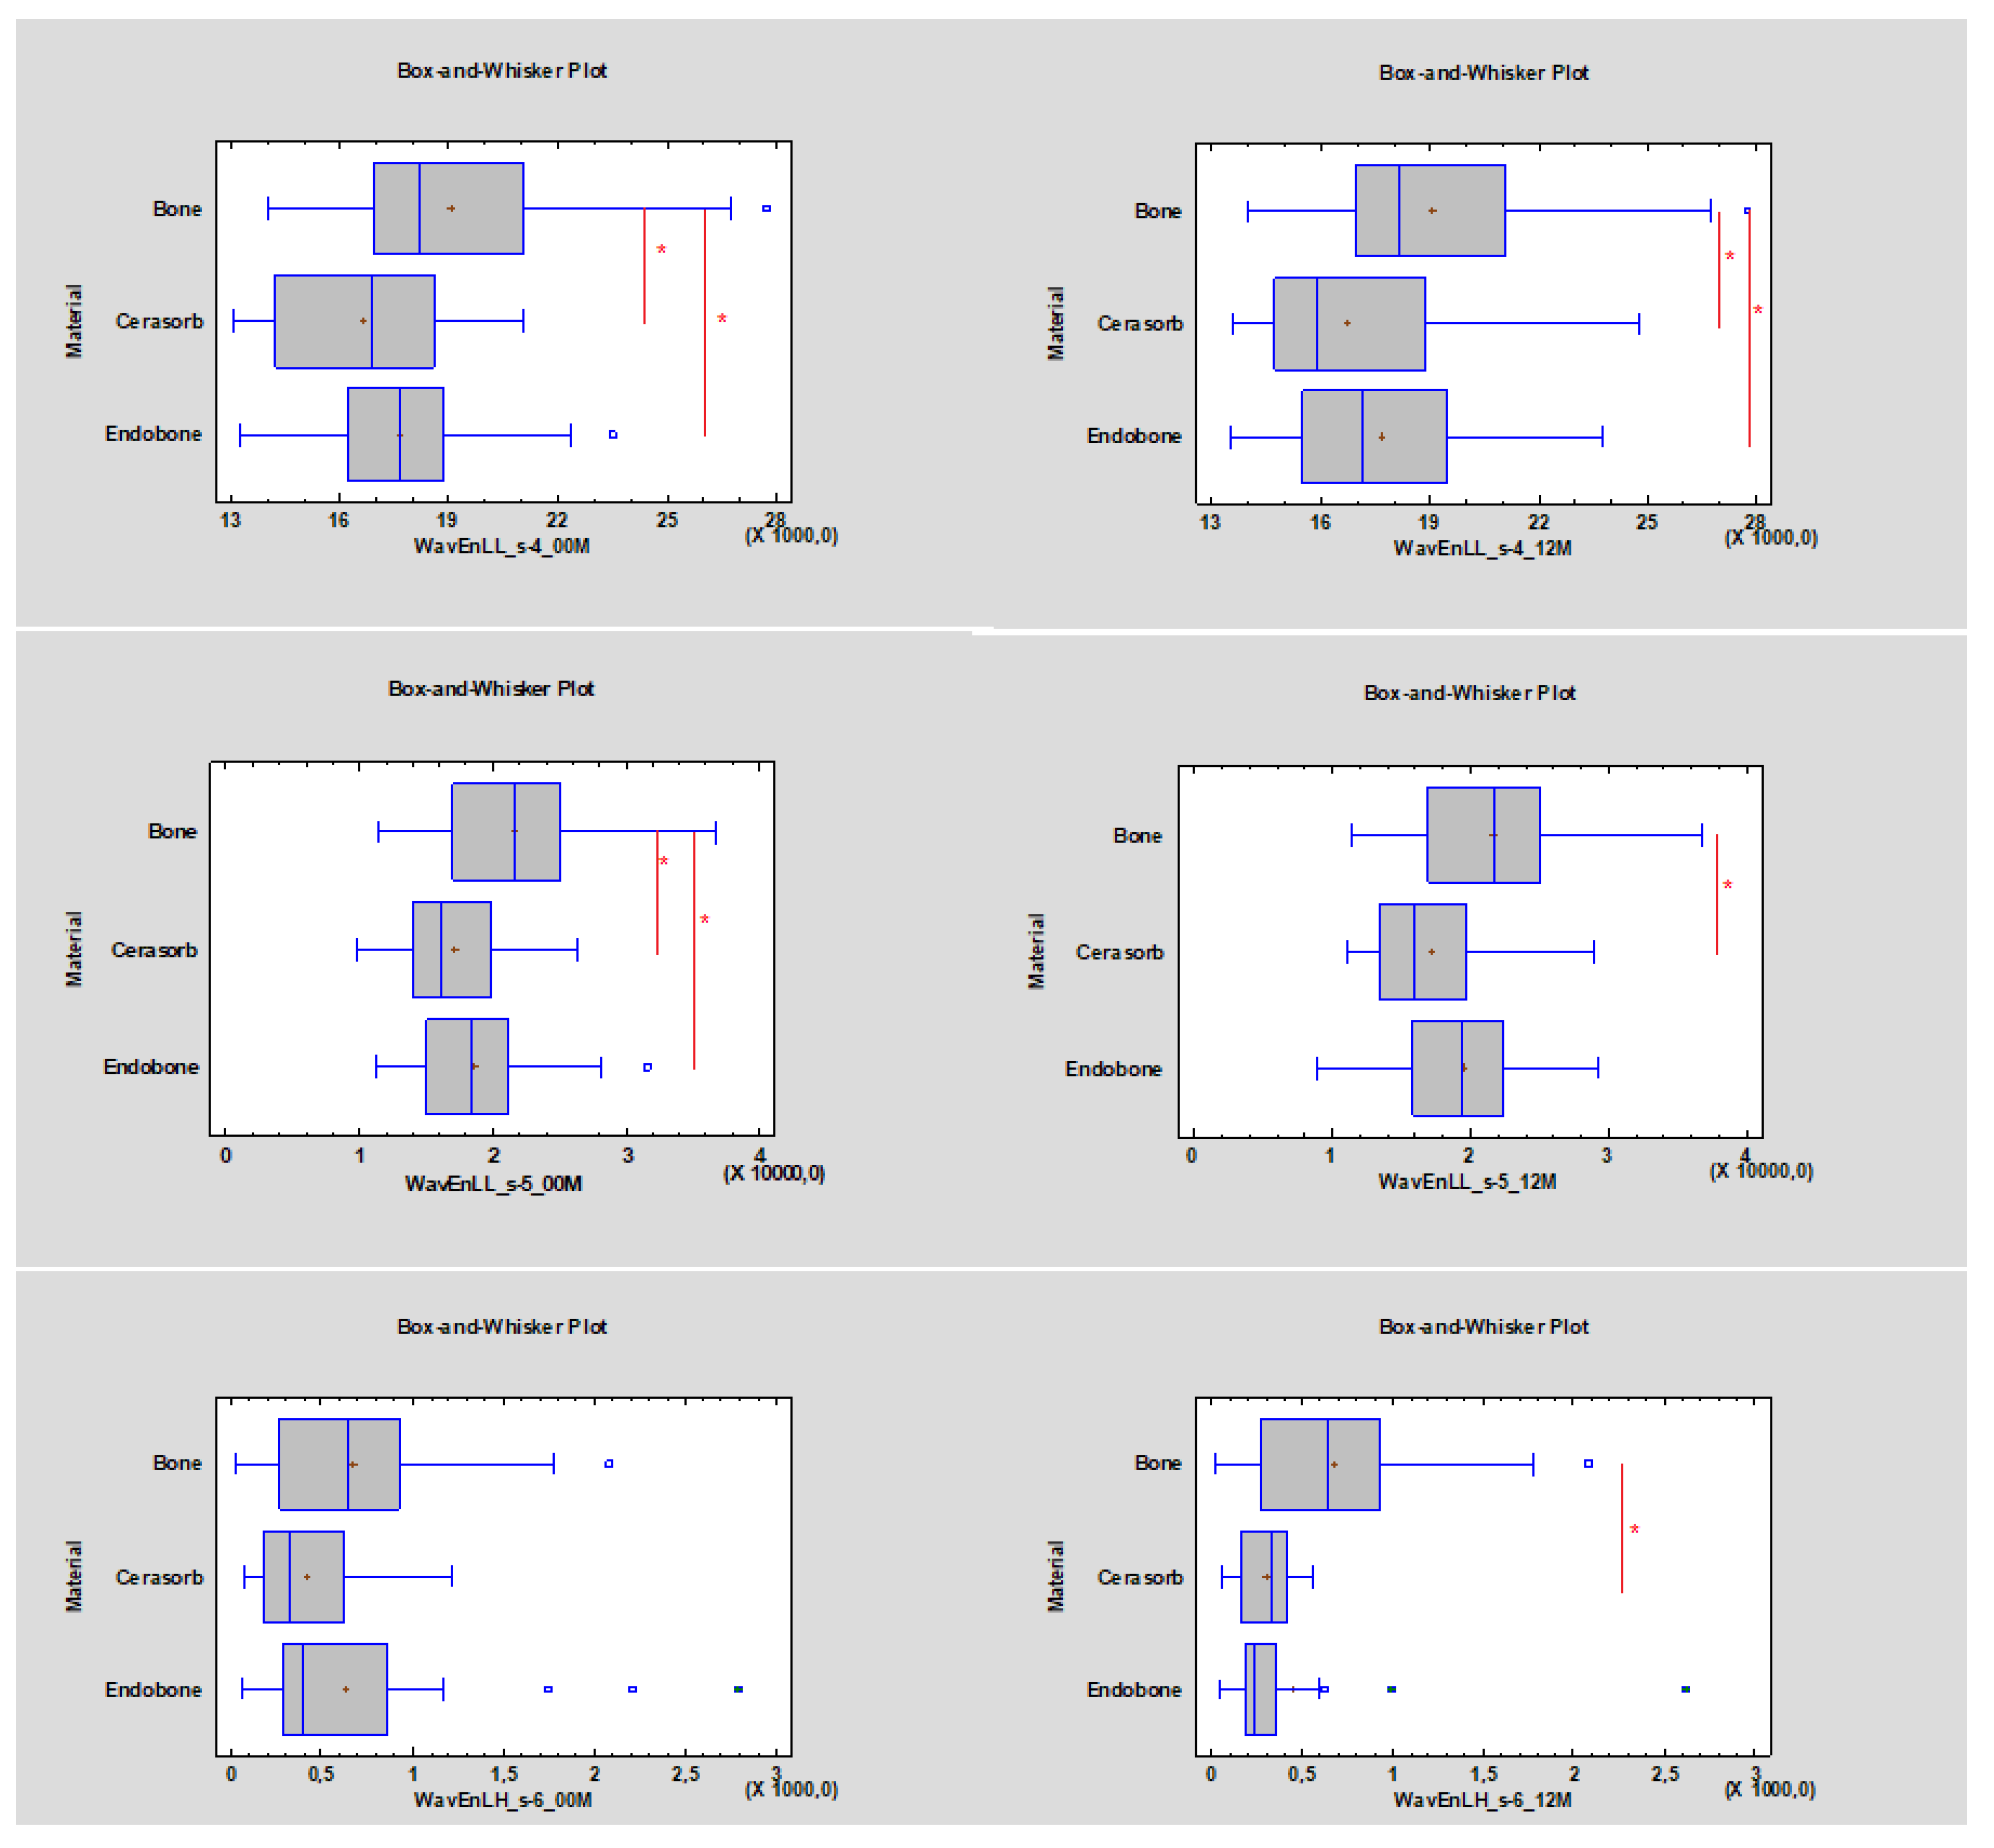

3. Results

- Wavelet energy (LL_s-4, LL_s-5, LH_s-6).

- ROI values lower than 17,910 (approximately 10,674) for WavEnLL_s-4 and lower than 18,577 (approximately 6485.85) for WavEnLL_s-5 represent cortical bone;

- WavEnLH_s-6 indicates bone tissue that is better than other wavelets, while ROI values between 484.04 and 523.24 indicate bone tissue instead of soft tissue (Table 2).

- The WavEnLL_s-4 value at 00 M for Cerasorb was 16,885, while the value for Endobone was 17,657. After 12 months the WavEnLL_s-4 value for Cerasorb was 15,876 (it decreased p < 0.05), while that for Endobone was 17,166 (p < 0.05);

- The WavEnLL_s-5 (p < 0.05) value at 00 M for Cerasorb was 16,073, while that for Endobone was 18,690. After 12 months the WavEnLL_s-5 value for Cerasorb was 15,907, while that for Endobone was 19,292 (p < 0.05);

- The WavEnLH_s-6 values after 12 months were 338.47 for Cerasorb and 231.82 for Endobone (p < 0.05).